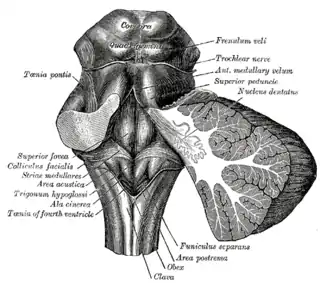

Cerebro anterior y medio. Vista posterolateral.

Cerebro anterior y medio. Vista posterolateral. Figura que muestra el modo de inervación de los músculos Recti medialis y lateralis del ojo.

Figura que muestra el modo de inervación de los músculos Recti medialis y lateralis del ojo. Tallo cerebral humano, vista posterior.

Tallo cerebral humano, vista posterior.